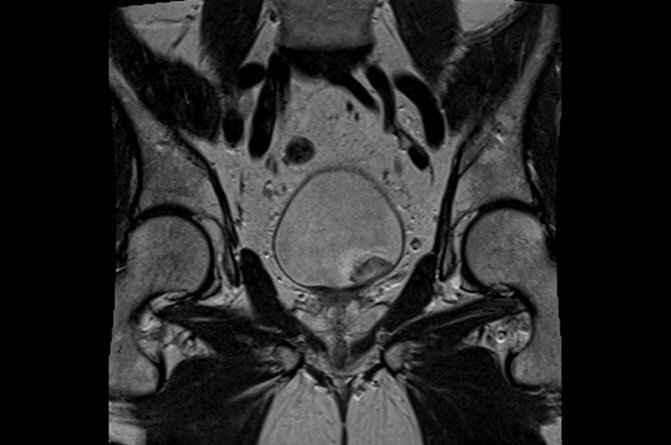

Высокая информативность - это основное преимущество МРТ органов малого таза. На полученных в ходе МР-сканирования графических изображениях органы мочеполовой системы фиксируются в максимальных подробностях. На томограммах хорошо видны: матка, яичники, влагалище у женщин и предстательной железы, мошонки, яичек, семенных пузырьков и пениса у мужчин, мочевой пузырь, нижняя часть мочеточников, прямая кишка, лимфатические узлы.

рак предстательной железы на МРТ